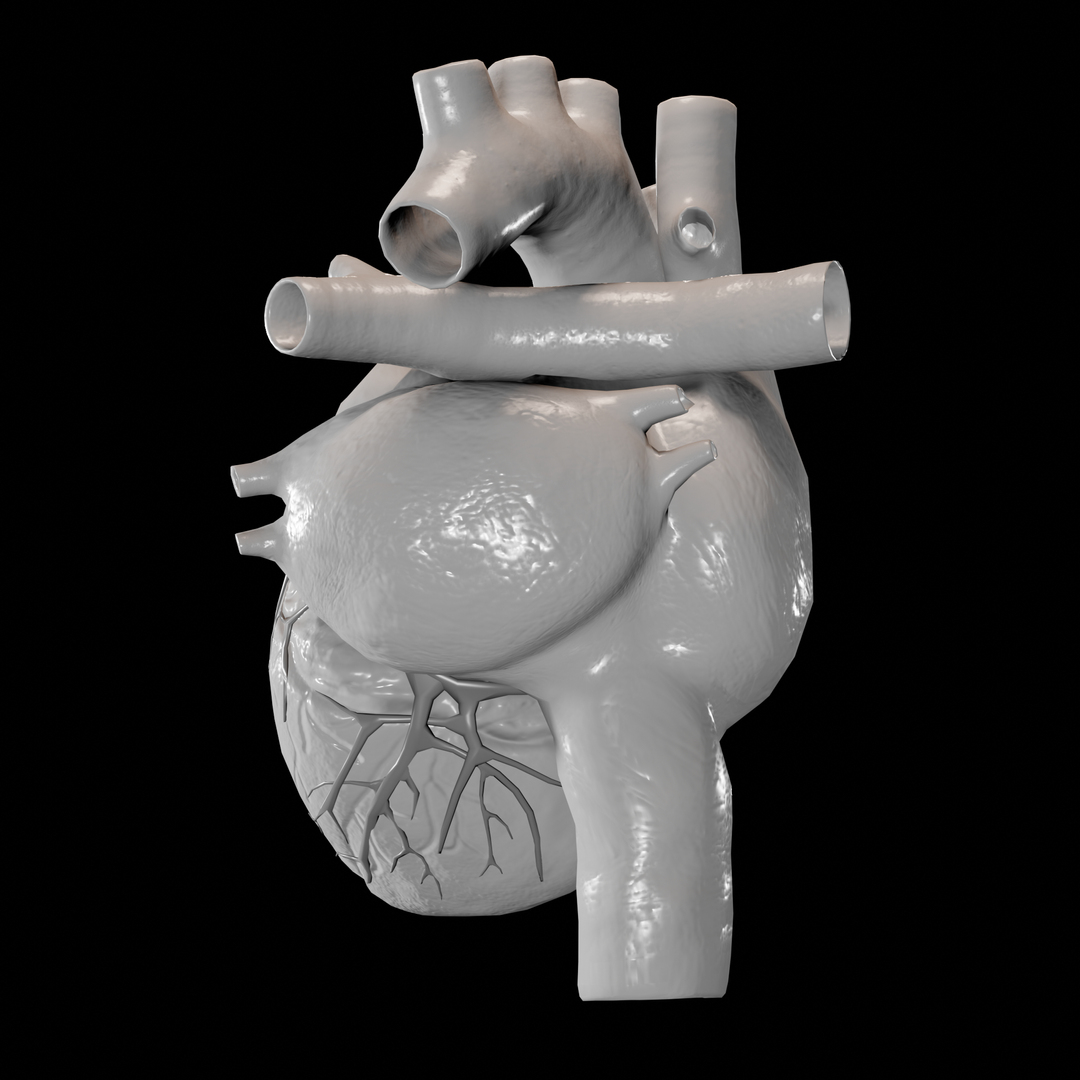

Animated Realistic Human Heart - Medically 3D asset  Zygote::3D Heart Model | Medically Accurate | Human Anatomy

Zygote::3D Heart Model | Medically Accurate | Human Anatomy  Zygote::Solid 3D Human Heart Model

Zygote::Solid 3D Human Heart Model  3D human heart anatomy model - TurboSquid 1283134

Human Heart Anatomy 1 3D model | CGTrader  How to draw realistic human heart||3d human heart sketch

Human Heart Anatomy 1 3D model | CGTrader  human heart anatomy 3d max